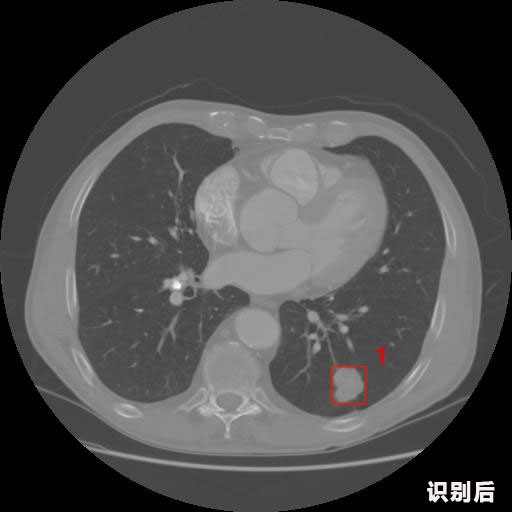

英特健康A(chǔ)I深度學(xué)習(xí)醫(yī)療圖像識別系統(tǒng)案例_胸部CT

1.發(fā)現(xiàn)肺結(jié)節(jié)的可能性為95.56%---位于框指數(shù)位置:[331.70554 366.13406 365.21707 403.96234]